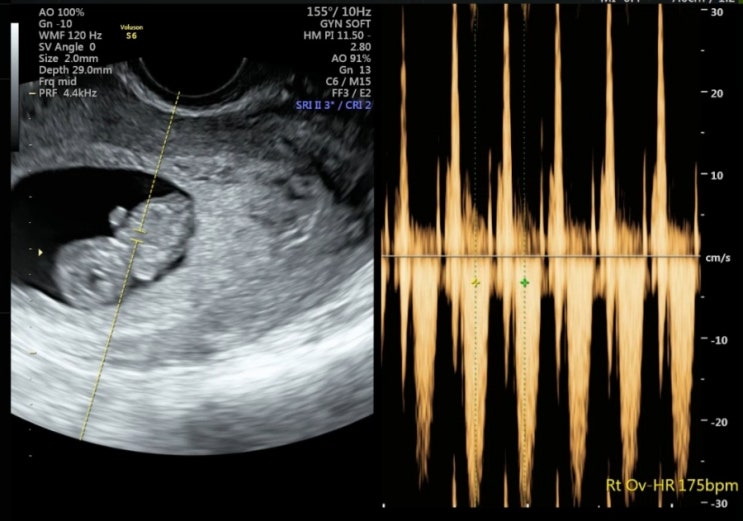

남편이 만들어준 떡국으로 시작한 1월 1일 새해. 진짜 2025년 들어오자마자 몸도 확 무거워지고 배도 많이 ...